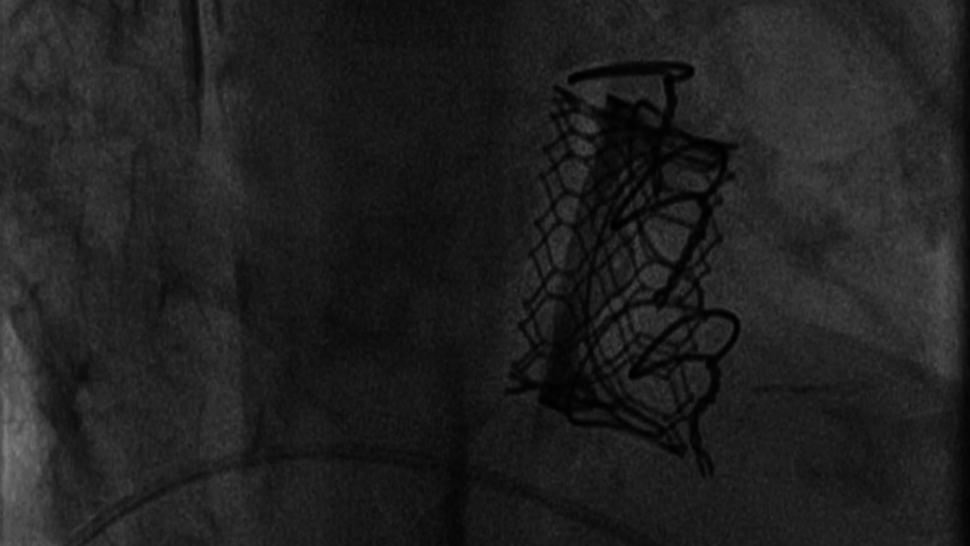

Bei einer Patientin mit hochgradiger Stenose eines degenerierten Mitralklappenersatzes wurde erfolgreich eine transseptale Valve-in-Valve-Implantation durchgeführt.

Die präinterventionelle Echokardiographie zeigte eine hochgradige Mitralklappenstenose mit einer effektiven Mitralklappenöffnungsfläche (MÖF) von 0,4 cm² sowie einem mittleren transmitralen Druckgradienten (Pmean) von 9–10 mmHg. Der Eingriff erfolgte vollständig kathetergestützt über einen transseptalen Zugang, ohne erneute Sternotomie. Die Implantation der Klappenprothese verlief komplikationslos. Postinterventionell zeigte sich eine deutliche hämodynamische Verbesserung mit einem mittleren transmitralen Druckgradienten von nur noch 2 mmHg.